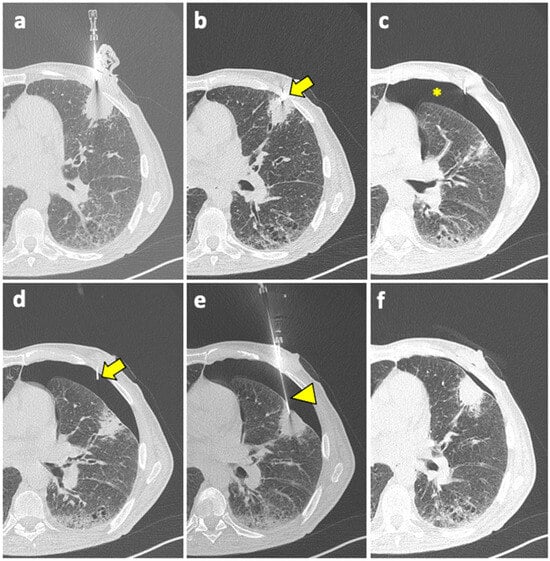

A useful technique in this setting is fusion imaging, which is defined as the process of overlapping imaging datasets from different modalities into a single composite imaging dataset. By using dedicated software, it is possible to overlap pre-procedural 18F-FDG PET/CT images to intra-procedural CBCT images, thus integrating functional and anatomical data, and to guide the needle towards the viable and metabolically active portion of the target lesion. An example of a biopsy guided by fusion imaging between CBCT and PET-CT is illustrated in Figure 5.